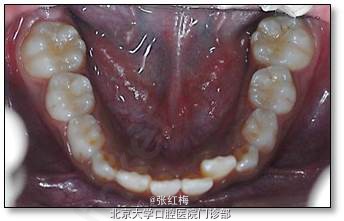

口腔卫生差;

11牙冠龈1/3折断,牙髓暴露约6×1mm2,灰紫色,略有增生,叩(±),不松,龈未见异常,

21牙冠龈1/3釉质横形隐裂,叩痛(-),不松,冷测同正常对照牙,龈未见异常;

11、21正中牙合及前伸牙合未见明显牙合创伤;

X线示:11、21发育9期,根管粗大,未见明显根折线,根尖周未见病变影,骨硬板清晰,未见牙槽突骨折线;

12、22、32、31、41、42叩痛(-),不松,冷测同正常对照牙,龈未见异常